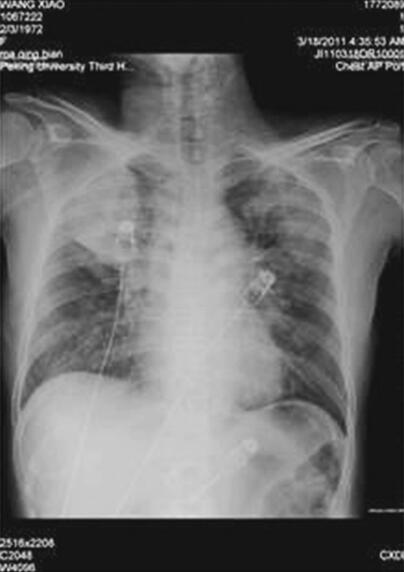

辅助检查:2011年3月18日血常规:WBC 15.97×109/L,N 89.5%,Hb 179g/L,PLT 142×109/L,肝肾功能、心肌酶正常,血糖19.8mmol/L,TNT(−),D-二聚体0.65ng/ml,BNP>5000pg/ml;尿常规:比重1.025,尿糖(++++),尿酮体(+++),尿蛋白微量;血气分析示:pH 7.17,PO2 68mmHg,PCO2 16mmHg,5.8mmol/L,SaO2 87%;胸片(1)示双肺纹理增多、模糊,可见多发片状模糊影,以右上肺为著,双肺门模糊,心影大小及形态未见异常,两膈面光滑,肋膈角锐利;胸部CT(图2)示双肺广泛分布斑片、团片状磨玻璃影,边界模糊,纵隔未见明显肿大淋巴结,心影无明显增大。诊断双肺多发病变——感染?肺水肿?ECG示窦性心动过速,非特异性T波改变。超声心动图示左心室壁运动弥漫减低,主动脉瓣反流(轻度),三尖瓣反流(轻度),LVEF 25%。

图1 入院时胸片示双肺纹理增多、模糊,可见多发片状模糊影,以右上肺为著,双肺门模糊,心影大小及形态未见异常